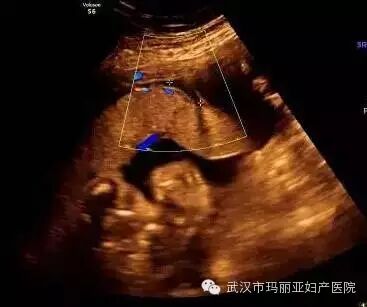

武汉玛丽亚妇产医院引进的世界领先的美国GE-E8四维彩超设备室目前世界上最先进、分辨率最高的彩色超声设备,具有即时立体成像、清晰准确的特点。

它能够多方位、多角度地观察宫内胎儿的生长发育情况,为早期诊断胎儿先天性体表畸形和发育异常提供科学依据。还能对胎儿的体表进行检查,如唇裂、脊柱裂、大脑、肾、 骨骼发育不良等,以便尽早的进行治疗。

玛丽亚美国GE-E8四维彩超排畸成功案例